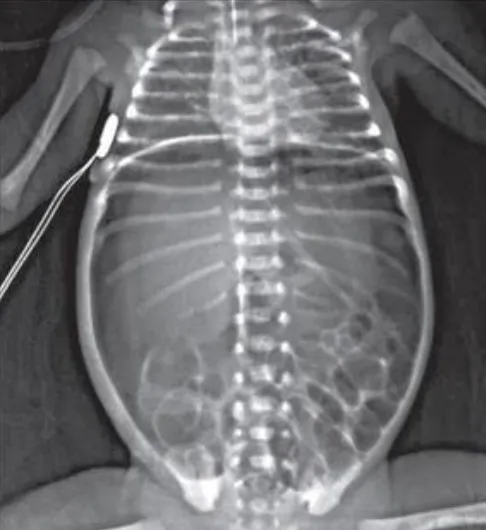

【114-1 醫學(四) 第3題】27 週出生的早產兒,開始餵食 12 天後,突然發生嗜睡、腹脹、含膽汁嘔吐、糞便帶血絲等症狀。其腹部 X 光檢查如下圖。發生此狀況時,下列何種處置最不適當?

詳解

破題關鍵

這題的解題核心是辨識早產兒腹部X光片上的典型病灶,並判斷在這種緊急情況下,哪些處置是必要的,哪些是禁忌。圖片中可見腸壁氣腫(pneumatosis intestinalis),這是壞死性腸炎(NEC)的經典影像學特徵。